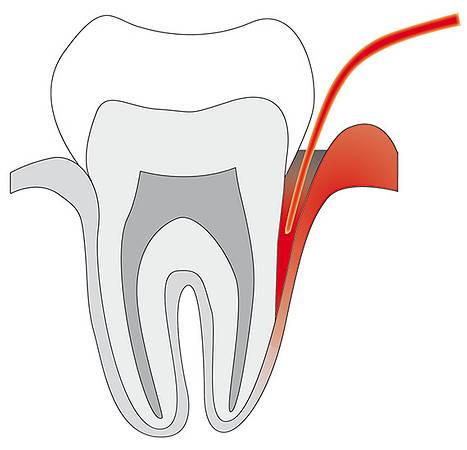

- Parodontitis (Zahnfleischtaschen)

- Parodontitis

© Cumdente